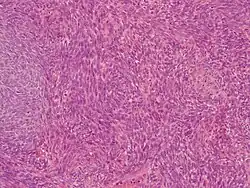

Histologie

Es existieren zwei unterscheidbare gewebliche Typen: zum einen ein biphasisch genanntes Synovialsarkom, das aus drüsenartig angeordneten Epithelzellen in einem Spindelzellverband besteht, und dem monophysisch genannten Typus, der nur aus Spindelzellen aufgebaut ist.